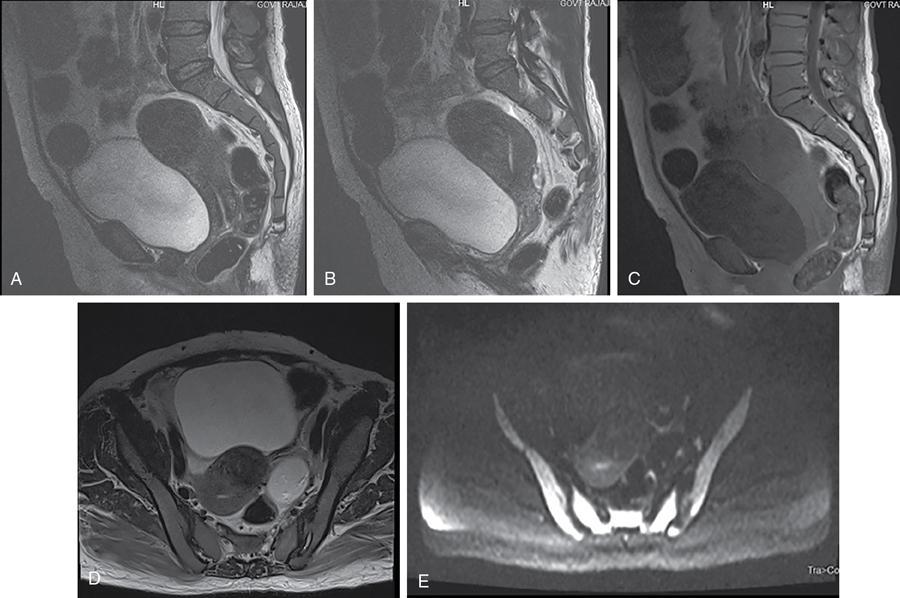

John De Lindsay, Sumathy, Vasumathy, Usha nandhini Ganeshan, N. Sundari ENDOMETRITIS Endometritis is defined as the inflammation of the uterine endometrial layer. Endometritis is frequently observed in the pregnant and postpartum population. Pelvic inflammatory disease (PID) and invasive gynaecological procedures are the most common causes of acute endometritis in nonobstetric population. Endometritis is the most complex asymptomatic and often presents with subclinical form of PID. Ultrasound may reveal minimal particulate endometrial fluid with mildly thickened endometrium showing increased vascularity. Computed tomography (CT) findings include a diffusely bulky uterus due by inflammation, mild fluid distension of endometrial cavity and striking endometrial enhancement in comparison to the adjacent myometrium due to mucosal hyperaemia. ‘Indistinct uterine border’ sign is observed in patients with endometritis, which is defined as the loss of distinction between the uterus and the adnexa. Since it is also observed in the cases of endometriosis or malignancy, it is a nonspecific sign. The age of the patient, clinical presentation, and the biopsy of endometrium helps in differentiating endometritis from other pathologies. UTERINE ARTERIOVENOUS MALFORMATION Uterine arteriovenous malformation (UAVM) is an abnormal connection between the arteries and the veins of the uterine myometrium without an intervening capillary bed. They were first reported by Dubreil and Loubat in 1926. They can be congenital or acquired. Even though UAVMs have varied presentation, uterine bleeding is the most common one. They often follow a pregnancy event. Episodic or occasionally torrential vaginal bleeding can occur. Congestive heart failure secondary to vascular steal can be a rare presentation due to a large UAVM. UAVM is most commonly an acquired condition. Pregnancy has a significant role in their pathogenesis. It is most commonly observed in reproductive age group. UAVMs are frequently observed in the postpartum period, few months after spontaneous miscarriage, surgical evacuation of uterus for miscarriage or medical termination of pregnancy. Infection, inflammation, retained products of conception (RPOC), gestational trophoblastic disease (GTD), gynaecologic malignancies, pelvic trauma and exposure to diethylstilboestrol can also lead to UAVMs. Few cases are also reported in young adolescent and postmenopausal females. UAVMs rarely are congenital and may be also associated with AVMs in other locations. Congenital AVMs Congenital AVMs have a central nidus with multiple feeding arteries and draining veins. In this condition, there is extension of the lesion beyond that uterus and multiple pelvic vessels other than uterine vessels draining into them. That cause of congenital AVMs are thought to be due to failure of embryological differentiation. With the progression of pregnancy, these vessels have the propensity to invade surrounding structures. Iatrogenic Acquired AVMs When the venous sinuses are incorporated into the scars of myometrium after the necrosis of chorionic villi, acquired malformations may arise. In contradiction to congenital AVMs, acquired AVMs multiple fistulous communication between the intramural arteries and the venous plexus. These AVMs may have either dual blood supply or a single supply from the uterine arteries and presents without nidus. Vaginal bleeding caused by pregnancy-related causes must be differentiated from UAVMs. Surgery/evacuation is the appropriate management for the former and the same is contraindicated in the UAVMs and hence an accurate definitive diagnosis is important. Grey-scale ultrasound findings are nonspecific and they are subtle heterogeneity of myometrium with multiple tubular or ‘spongy’ anechoic or hypoechoic areas. In spite of varied presentations such as an intramural uterine, endometrial or cervical mass-like lesions or prominent parametrial vessels, it has minimal mass effect. On colour Doppler, within the myometrium, a region of increased vascularity and most commonly with aliasing is seen. A group of vessels traversing the myometrium running perpendicular to and into the endometrium, from the arcuate vessels, can be seen. It is not specific, as they are also observed in RPOC, GTD, placental polyp and vascular endometrial neoplasm. In pulsed Doppler, multidirectional turbulent flow with intense vascularity can be seen with high peak velocity (mean peak systolic velocity [PSV] = 136 cm/s) and low resistance (mean resistance index = 0.3) flow. The arteries have low pulsatility while the draining veins are pulsatile and show high velocity flow. Magnetic resonance imaging (MRI) offers noninvasive confirmation of the diagnosis of UAVM. T1-weighted and T2-weighted images show multiple serpentine signal voids along the uterine wall, endometrial cavity and parametrium. Contrast-enhanced MR angiography shows intensely enhancing complex serpentine abnormal vessels with early venous return. Catheter angiography can be reserved only for women who require embolization of the AVM. The consent for both diagnostic angiography and therapeutic embolization should be obtained simultaneously to avoid repeat therapeutic procedures. Management of UAVM depends on: UAVM can be treated with medical therapy with hormones, uterine artery embolization or with definitive hysterectomy. Once the diagnosis of a UAVM is confirmed, the treatment option depends on the clinical condition of the patient. The size of the AVM bears no correlation to the need for embolization. Timmerman et al. found that AVMs having PSV of at or above 0.83 m/s, most often requires embolization. Also, the vascular malformation with PSV value below 0.39 m/s does not require embolization. Placental bed subinvolution, enhanced myometrial vascularity (EMV), molar pregnancy or RPOC are the other causes of uterine mass vascular malformations which usually has a mean PSV of 0.52 m/s and does not require embolization. Transcatheter targeted uterine artery embolization is indicated in selected cases, if bleeding persists to a degree that blood transfusions are required to maintain haemodynamic stability or multiple repeated acute hospitalizations. This is preferred over surgical management owing to its immediate minimally invasive and fertility sparing benefits. Gelfoam had been suggested earlier as the material of choice for embolization. Various other embolic materials like polyvinyl alcohol, Histoacryl glue, stainless steel coils, detachable balloons, and haemostatic gelatin are also used nowadays. Normal intrauterine pregnancies after embolization have been reported, proving that an adequate collateral blood supply can develop to support a full-term pregnancy. Gestational Trophoblastic Disease RPOC: Presence of endometrial pathology rather than myometrial origin. FIBROIDS Leiomyomas, also known as fibroids or myomas, are the most common gynaecologic neoplasms, occurring in 20%–30% of women of reproductive age. Symptomatic uterine fibroid accounts for about 30% of hysterectomies performed for women older than 18 years of age and 41% of hysterectomies performed for women from 44 to 64 years of age. Leiomyomas are the benign neoplasms made up of whorled fascicles of smooth muscle and fibrous connective attached to the uterine muscular wall. Even in the absence of true capsule, leiomyomas are well circumscribed and contains a pseudocapsule. Its size is variable, ranging from tiny microscopic to large tumours filling the abdomen. Most commonly, the uterine leiomyomas are seen in the myometrium of uterine corpus. However, it is also seen in the cervix (<5% of cases). On the basis of the location, uterine fibroids are classified as submucosal, intramural or subserosal. This classification is of clinical significance because the symptoms and treatment vary among these subtypes of leiomyomas. Submucosal myomas are further subclassified as 0, I and II depending on the percentage within the endometrial cavity. The first two categories can be removed hysteroscopically (Table 11.15.3.1). Pedunculated leiomyomas are attached to the uterus by a stalk and may be either intracavitary or exophytic (narrower than 50% of diameter of myoma). Rarely, a submucosal fibroid may grow pedunculated and extends into the cervical canal or vaginal canal and its prevalence is about 2.5%. Pedunculated subserosal leiomyomas may undergo torsion, resulting in infarction accompanied by pain. Lateral growth into broad ligament leads to intraligamentous leiomyoma (Table 11.15.3.1). Rarely, a pedunculated leiomyoma may become detached from the uterus (parasitic leiomyoma). Depending on the location, size and number of uterine fibroids, it has varied presentation. Symptoms caused by leiomyomas are classified into three different categories such as abnormal uterine bleeding, pelvic pressure and pain and reproductive dysfunction. Submucosal leiomyomas and intramural leiomyomas are often associated with menorrhagia (Table 11.15.3.1). Because of leiomyoma, uterus may be irregularly shaped and causes symptoms based on their locations. Anterior leiomyomas cause urinary symptoms, whereas the posterior leiomyomas cause constipation. Ureter may be compressed by broad ligament leiomyomas and presents as hydroureter or hydronephrosis. In case of degeneration or torsion of a pedunculated leiomyoma, acute pain may be the presentation. Leiomyomas are an infrequent primary cause of infertility. Malpresentation, pregnancy failures and dystocia are reported. Ultrasound is the first-line imaging modality because it is a cost-effective portable real-time examination that provides good anatomic detail. Leiomyomas appear as a well-defined round or oval hypoechoic solid mass. It is mostly associated with posterior shadowing possibly due to calcifications or interface of the margins of the leiomyoma with the normal myometrium. Degeneration or lipoleiomyoma can be suggested when there is internal echo-poor or hyperechoic foci, respectively. The presence of hypervascularity in a large solitary uterine mass can identify suspicious masses, such as a leiomyosarcoma (LMS). Another study found that there is an increased detection rate of uterine sarcomas while using a cut-off value of 41 cm/s. In the assessment of a uterus enlarged with multiple leiomyomas, ultrasound has FOV limitations. Likewise, it has limited role in the assessment of retroverted uteri, pedunculated subserosal myomas and concomitant adnexal processes. Little has been reported regarding sonographic changes after MR HIFU and uterine fibroid embolization (UFE). Differential diagnosis has been discussed in Table 11.15.3.2. Hyperechoic unlike a myomatous polyp which appears hypoechoic Heterogeneous endometrium with little mass effect Enlarged uterus and a deformed contour are the most common computed tomography (CT) findings. Even though CT is the primary modality for the staging of cancers, it has limitation of reduced contrast resolution for the assessment of focal myometrial masses, and associated with risk of ionizing radiation. Also, in delineating the zonal anatomy for accurate localization of leiomyomas and LMSs, CT is inferior to magnetic resonance imaging (MRI). More often dense or amorphous calcification is seen. Almost exclusively, on plain radiography or CT, these patterns of calcification favours the diagnosis of leiomyoma. Ring-like calcification at the margins of a leiomyoma is a rarely observed pattern, which represents the thrombosed veins. Positron emission tomography (PET)/CT is an ideal modality for the confirmation of malignancy and also helps in detection of metastasis and recurrence. In a small study of patients with histopathologically confirmed uterine sarcoma found that on comparing with the findings of MRI and ultrasound with power Doppler imaging, the results of fluorodeoxyglucose (FDG) PET examinations were 100% positive. However, it has limitations such as increased false-positive rate and reduced widespread availability. MRI appearance of leiomyomas: MRI is considered as the most accurate imaging technique for the detection and localization of leiomyomas. In determining the presence and location of leiomyomas in infertile women before myomectomy, MRI has been shown to be more accurate and sensitive than US or hysterosalpingography. Nondegenerated uterine leiomyomas usually has a typical MRI appearance of (Table 11.15.3.4) well-circumscribed masses with homogeneously decreased T2-weighted signal intensity. TABLE 11.15.3.3 Note: SI, signal intensity; ADC, apparent diffusion coefficient. Compared with that of normal smooth muscle myometrium. Degenerated leiomyomas have varied imaging appearances on T1-weighted, T2-weighted and contrast-enhanced images as described in Tables 11.15.3.4 and 11.15.3.5. Hyaline Oedema *Common *50% cases *Usually peripheral Cystic Myxoid Carneous, red, or UAE associated Calcific Leiomyoma variants (Tables 11.15.3.4 and 11.15.3.6): There are several, such as mitotically active, cellular and atypical leiomyomas, as well as smooth muscle tumours of uncertain malignant potential (STUMP). On histopathological examination, the nondegenerated fibroids are made up of goals of uniform smooth muscles with varied amounts of collagen. Cellular leiomyomas, which are composed of compact smooth muscles cells only with no collagen, will demonstrate increased T2-weighted signal intensity and homogeneous enhancement. There is a greater risk of recurrence in case of atypical leiomyomas and uterine STUMP. The patients who had undergone myomectomy and were found to have atypical leiomyoma, must be under surveillance with an annual pelvic ultrasound or MRI. Since the recurrences may presents as pelvic or abdominal masses or as pulmonary metastases, for all the patients with STUMP lesions, routine physical examinations, including pelvic examinations and the baseline CT of the chest, abdomen and the pelvis are recommended for every 6 months for 5 years and then annually thereafter. In addition, prompt re-exploration and staging is recommended for patients with STUMP who have undergone a morcellation myomectomy. An aggressive imaging surveillance is considered, when the disease is present. Atypical leiomyomas and STUMPs routinely express progestin receptors; however, because of the low recurrence rates, there is no role for adjuvant hormonal therapy. Atypical uterine masses can be treated surgically with hysterectomy or myomectomy. Histologic subtype Cellular leiomyoma Round or oval Single large lesion with absence of coexistent adenomyosis Responds to GnRH analogues Cured with surgery No need for follow-up Lipoleiomyoma Well defined: round or oval STUMP Round or oval Intense surveillance Note: SI, signal intensity; ADC, apparent diffusion coefficient; UAE, uterine artery embolization; STUMP, smooth muscle tumours of uncertain malignant potential. Being a benign neoplasm, fibroids usually have a pushing border and rounded edges. But, specific types of fibroids represent growth pattern variations, such as intravenous leiomyomatosis, metastasizing leiomyoma, diffuse leiomyomatosis and peritoneal disseminated leiomyomatosis. Retroperitoneal growth and parasitic growth are the other atypical growth patterns. Even cervical and vaginal leiomyomas may show growth pattern. It is important to note that adenomyosis and focal myometrial contraction can coexist and distinction is important at preprocedure imaging (Table 11.15.3.7).